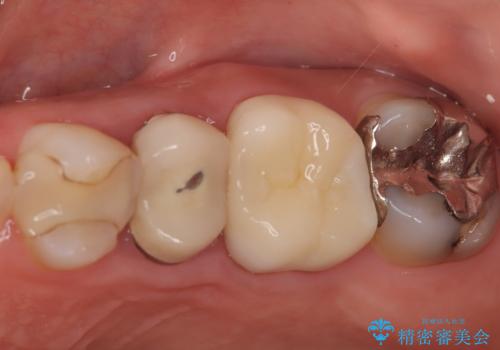

左上第一小臼歯のインプラント治療

- 患者様は、左上第一小臼歯の垂直性歯根破折が確認され、抜歯が必要となりました。本来、抜歯即時埋入を適用できるケースでしたが、患者様のご都合によりブリッジとインプラントで一度悩まれるとのことで待時埋入となりました。治療計画では、上顎の骨の状態を慎重に評価し、デンサーバーを用いてドリリングを行うことで、上顎洞粘膜を傷つけずにインプラントを埋入する方法を選択しました。埋入後の安定を確保するため、術後の経過観察を慎重に行います。